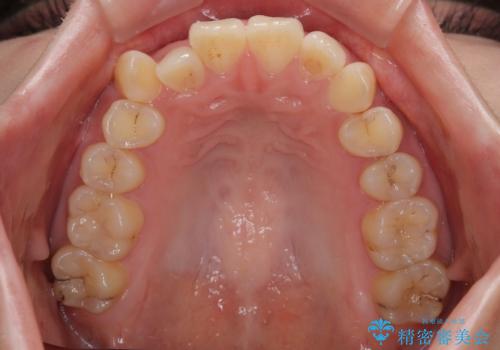

- 上下前歯のデコボコを気にして来院された患者様です。

ワイヤー矯正でもマウスピース矯正でも可能でしたが、短期間で、自身の手を煩わせることなく治療を行いたいとのことで、ワイヤー装置にて矯正治療を行うこととしました。

僅か8ヶ月という短期間で、綺麗な歯列に仕上がりました。